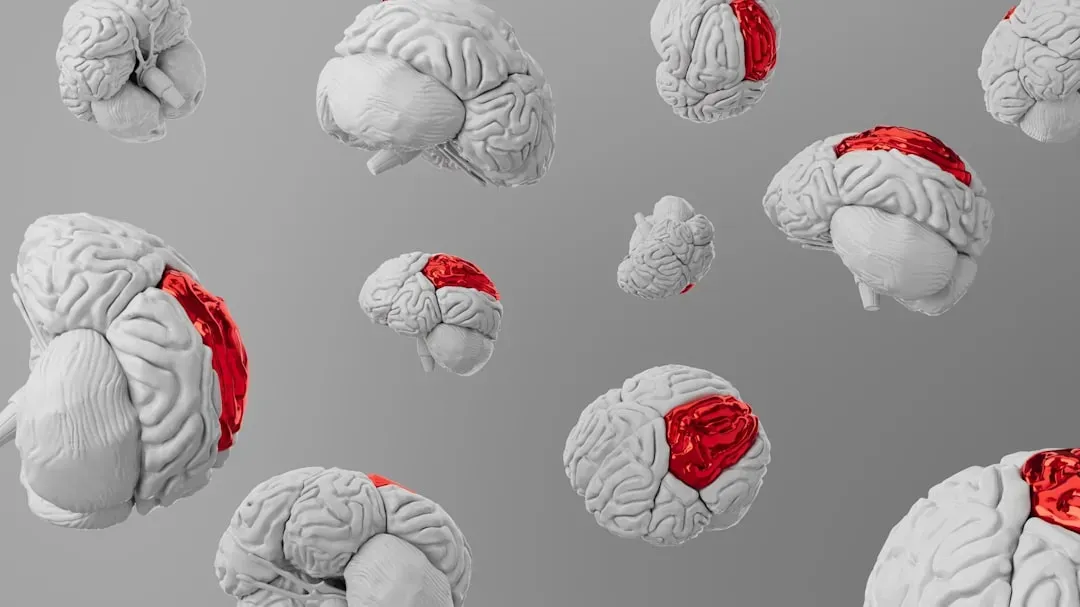

Mapping Neurological Conditions Highlighted Areas in the Brain ...

Premium Photo | Mapping Neurological Conditions Highlighted Areas in ...